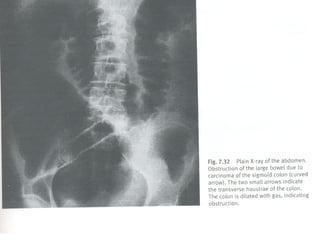

 Radiologia simples e com cantrast-barium